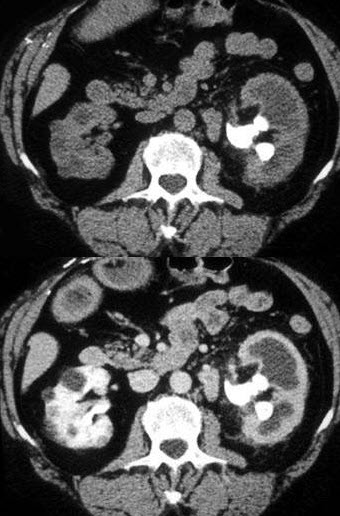

患者溃疡性结肠炎并最近黄疸发作,结合图像,最可能的诊断为( )

A:胆管癌

B:肝细胞癌

C:肝脓肿

D:肝炎

E:胆囊癌